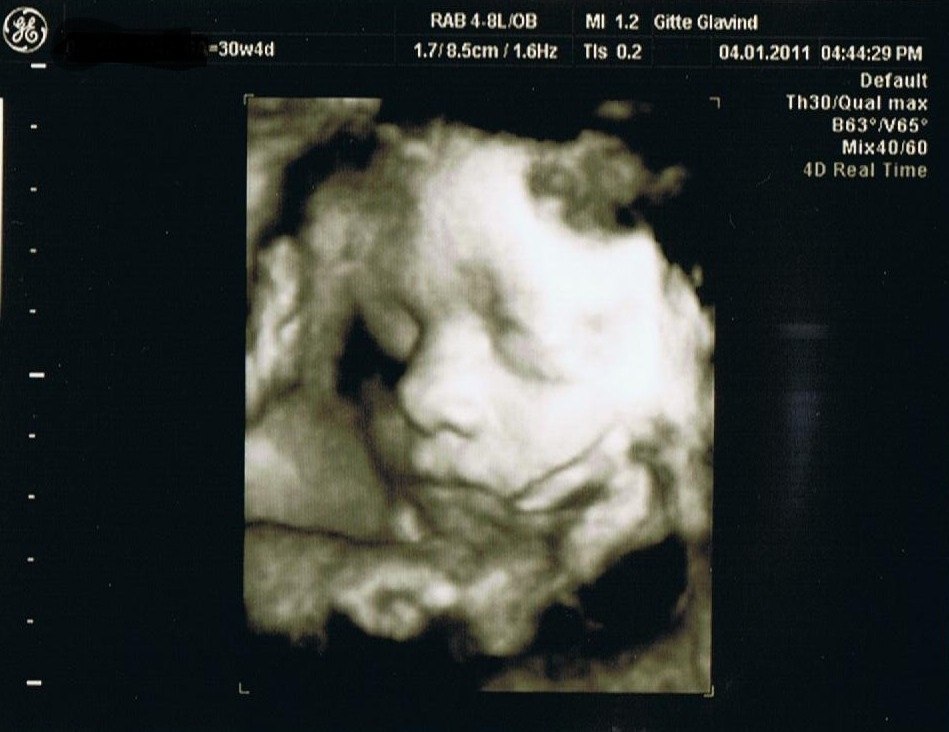

Lige 2 billeder fra skanningen, kan varmt anbefale det. Det er en utrolig oplevelse

Vedhæftede fotos (klik for at se i fuld størrelse)

Det var en utrolig dejlig oplevelse. Det bliver også sjovt at vise ham når han bliver gammel nok til at forstå det. Fik også en dvd med hjem af hele skanningen.